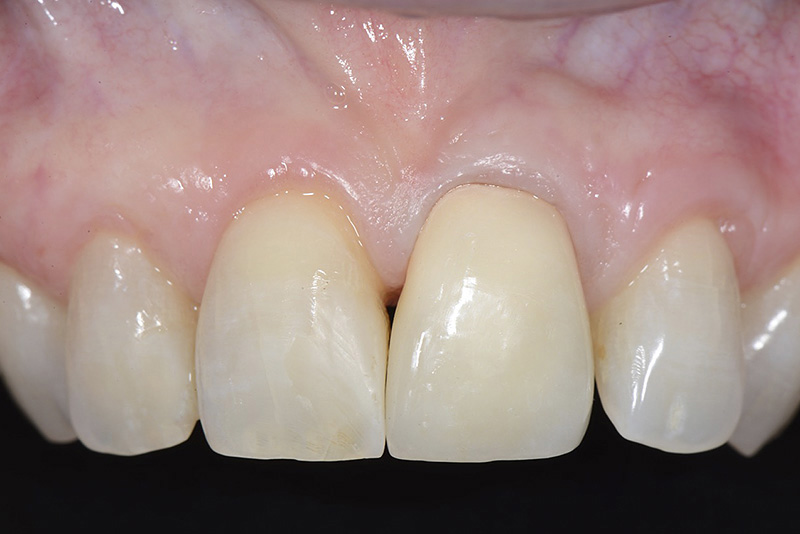

PREMESSA: in seguito all’estrazione dell’incisivo laterale superiore di destra, resasi necessaria per cause batteriche, si decide di affrontare il caso con il posizionamento di un impianto in sostituzione dell’elemento mancante dopo guarigione del sito infetto. Con tecniche rigenerative sia dei tessuti ossei mancanti a causa dell’infezione pregressa, sia dei tessuti gengivali che appaiono inizialmente troppo spostati in alto, si ripristina una corretta morfologia delle parabole (contorni) gengivali e delle papille interdentali (triangoli di gengiva tra due denti vicini).

Vengono utilizzati 2 tipi di provvisori: il primo, cementato ai denti vicini, viene utilizzato dal momento dell’estrazione del dente fino ad impianto osteointegrato (circa 6 mesi); il secondo, avvitato direttamente all’impianto, ha una funzione di prova estetica ma soprattutto di guida per la maturazione dei tessuti gengivali peri-implantari portandoli verso la maturazione completa prima di posizionare la corona finale in disilicato di litio.